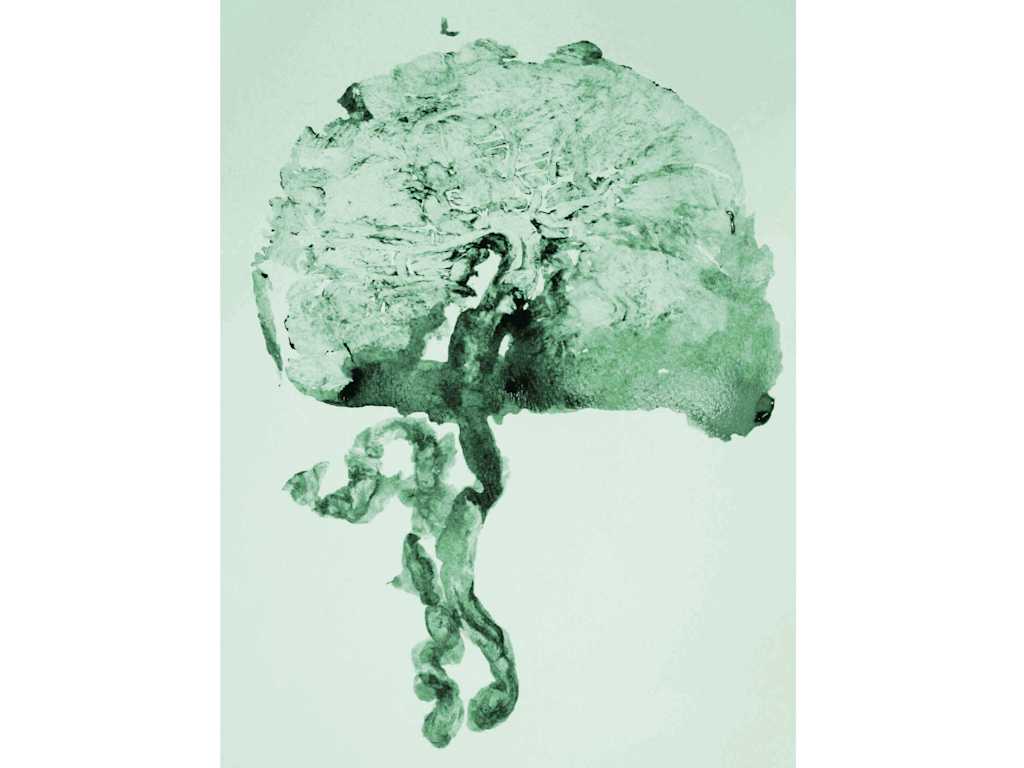

Die Embryonalentwicklung Des Menschen Springerlink